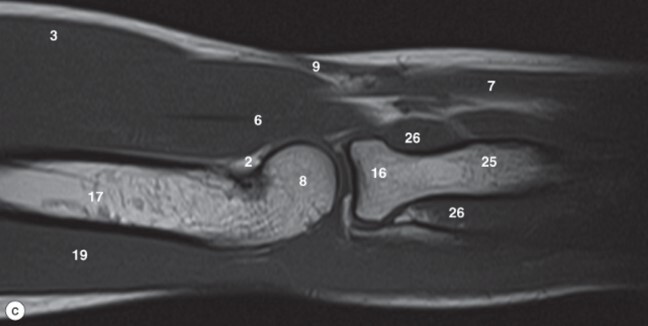

Label 3,6,8,8,16,17,19,25

3=Biceps brachii muscle

6=Brachialis muscle

8=Capitulum of humerus

9=Cephalic vein

16=Radial head

17=Humerus

19=Triceps brachii

25=Radius